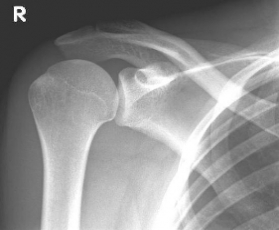

right: X-ray of a healthy shoulder joint

X-rays can be used to reliably diagnose the extent of joint wear. In the case of severe osteoarthritis, for example, the joint space and the formation of jagged edges (osteophytes) can be detected. If additional damage to the tendons of the shoulder (rotator cuff) is suspected, ultrasound examination (sonography) or magnetic resonance imaging (MRI) can help clarify the situation.